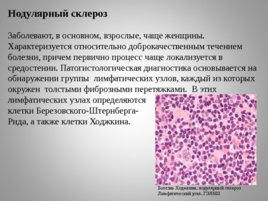

Микропрепараты: Лимфогранулематоз и Нодулярный Склероз

Раздел: Секреты мастерства